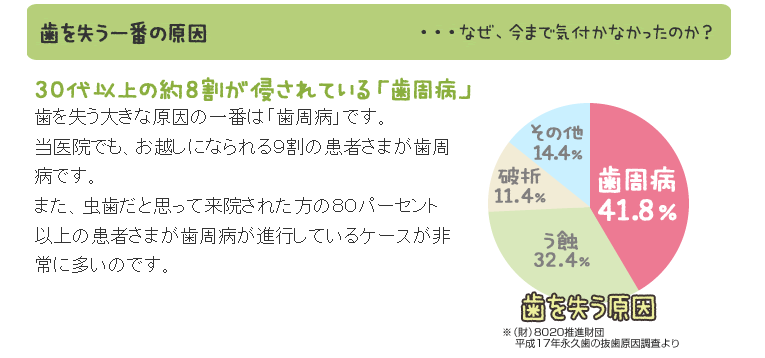

歯周病は歯を支える骨が溶ける病気です。

予防するには定期的な歯の掃除だけでは片手落ちです。